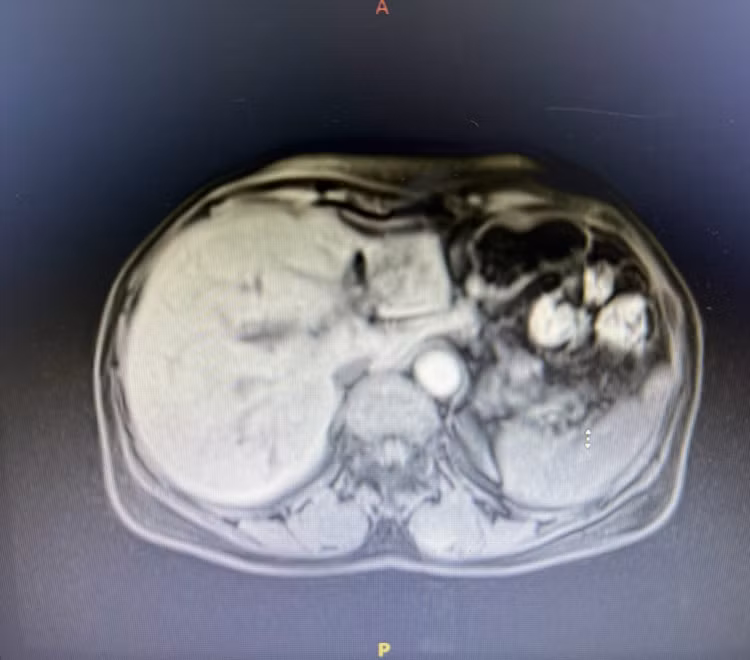

Tại đây, sau khi xem xét các thông tin về siêu âm, ThS.BS. CKII. Phan Văn Sơn đã chỉ định người bệnh chụp MRI (cộng hưởng từ) vùng gan - mật, kết quả cho thấy có một lượng lớn sỏi trong ống mật chủ đồng thời nhiều viên sỏi nhỏ và túi chứa sỏi len lỏi khắp trong đường mật gan trái.

Dựa trên các kết quả chẩn đoán hình ảnh, bác sĩ nhận định sỏi đã hình thành lâu trong ống mật chủ dẫn đến tắc mật, đồng thời ống gan trái bị chít hẹp khiến cho toàn bộ thùy gan trái của bệnh nhân đã bị xơ teo và tạo các túi sỏi.

| Hình ảnh CT vùng gan tổn thương của bệnh nhân. Ảnh BVCC |